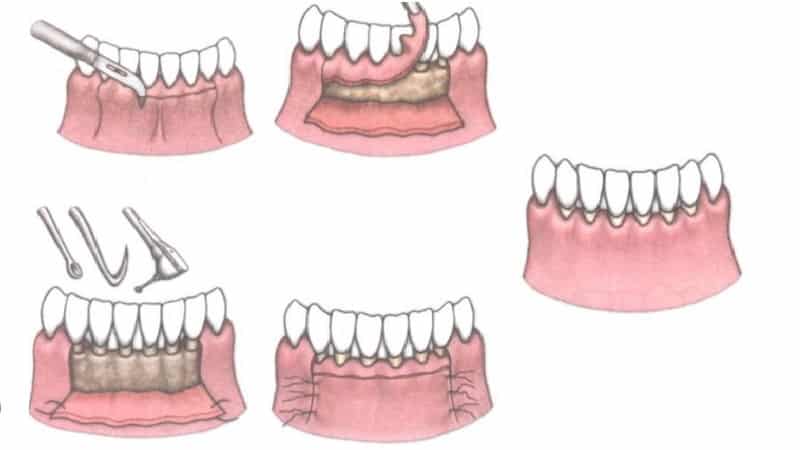

Открытая процедура включает в себя отслоение слизистой ткани десен хирургом-пародонтологом. Для этого врач делает небольшие разрезы в области шейки зубов. Полученные лоскуты отводятся от кости, обнажая зубные корни и участки разрушенной кости. На этом этапе врач получает полный доступ к поддесневым камням и налету, а также грануляционной ткани. Он удаляет эти патологические образования (включая карманы) с помощью хирургических кюрет. В современных клиниках также используется ультразвуковой скалер для выскабливания заместительной ткани и камней. Таким же образом может быть удален пародонтальный карман.

После этого врач проводит антисептическую обработку области. После удаления грануляционной ткани в костной ткани остаются пустоты. Дантист заполняет их костью, полученной синтетическим путем.

Этот искусственный материал способствует восстановлению собственной ткани, что позволяет значительно уменьшить глубину пустот.

Заключительным этапом является наложение швов в области межзубных сосочков. Также на эту зону накладывается специальная повязка, защищающая рану от инфекции и способствующая регенерации ткани. Швы удаляются врачом через 10 дней.